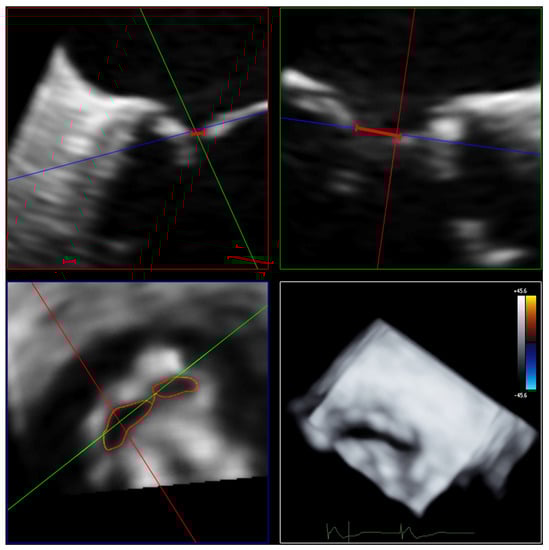

Measurements of 3D VCA and AROA were made using the full-volume 3D color Doppler datasets with the recommended limiting velocity of 50–70 m/s. The 3D VCA was planimetrically fitted to the minimum cross-sectional area of the regurgitation jet in the full-volume 3D color Doppler dataset (Figure 3). Considering the constraints of a curved plane, a manual measurement of the color Doppler of the cross-sectional plane was performed, excluding fractions of too-low velocities to determine the 3D VCA. Attention was paid to a constant setting of brightness and contrast and a fixed setting of color intensity at 50% values and smoothening.

Figure 3. Determination of 3D VCA using multiplanar reconstruction in the 3D color Doppler dataset. Echocardiographic images with 3 slice planes and 3D reconstruction (lower right) of the 3D color Doppler dataset (mid-systolic). Planimetric fitting of the 2 upper planes along the course of the color Doppler jet; third plane (lower left) adjustment orthogonal to planes along the jet and finding the minimal cross-section of the regurgitation jet using translation and tilting of the third plane; manual measurement of the minimal cross-sectional plane using outlining. Abbreviations: 3D = three-dimensional; VCA = vena contracta area.